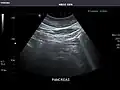

Pancreas: Visualized portions unremarkable.

Pancreas -